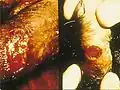

- Lésions du pénis

Donovanose chez l'homme